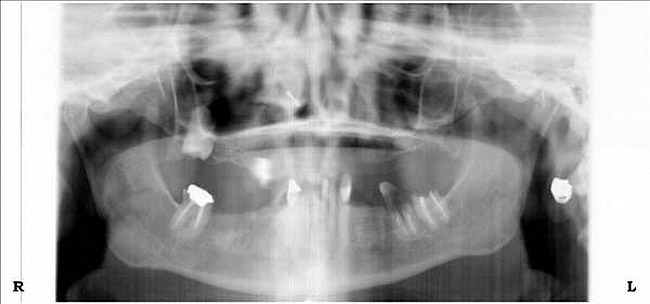

Figure 10a  Supra-eruption of the opposing arch, thus diminishing crown height space.

Figure 10a

Figure 10b  Supra-eruption of the opposing arch, thus diminishing crown height space.

Figure 10b

Diminished crown height space has several different solutions which depend on the patient’s anatomical limitations as well as his or her perceived needs. If the problem is the opposing arch, the solution may be fixed prosthodontics to level the occlusal plane (Figure 10A through Figure 10D). It may be intrusion of teeth with orthodontics or some combination of the two. If there is too little crown height space and the patient is edentulous, the solution may be to increase the vertical dimension of occlusion (VDO) with a removable prosthesis.17 If the patient has a partial dentition, it may involve traditional fixed prosthodontics to alter the VDO.18 The patient may need a surgical approach, such as an osteoplasty, before implant placement (Figure 11A and Figure 11B). However, without an initial diagnosis, there is no way of formulating a solution to an unknown problem.